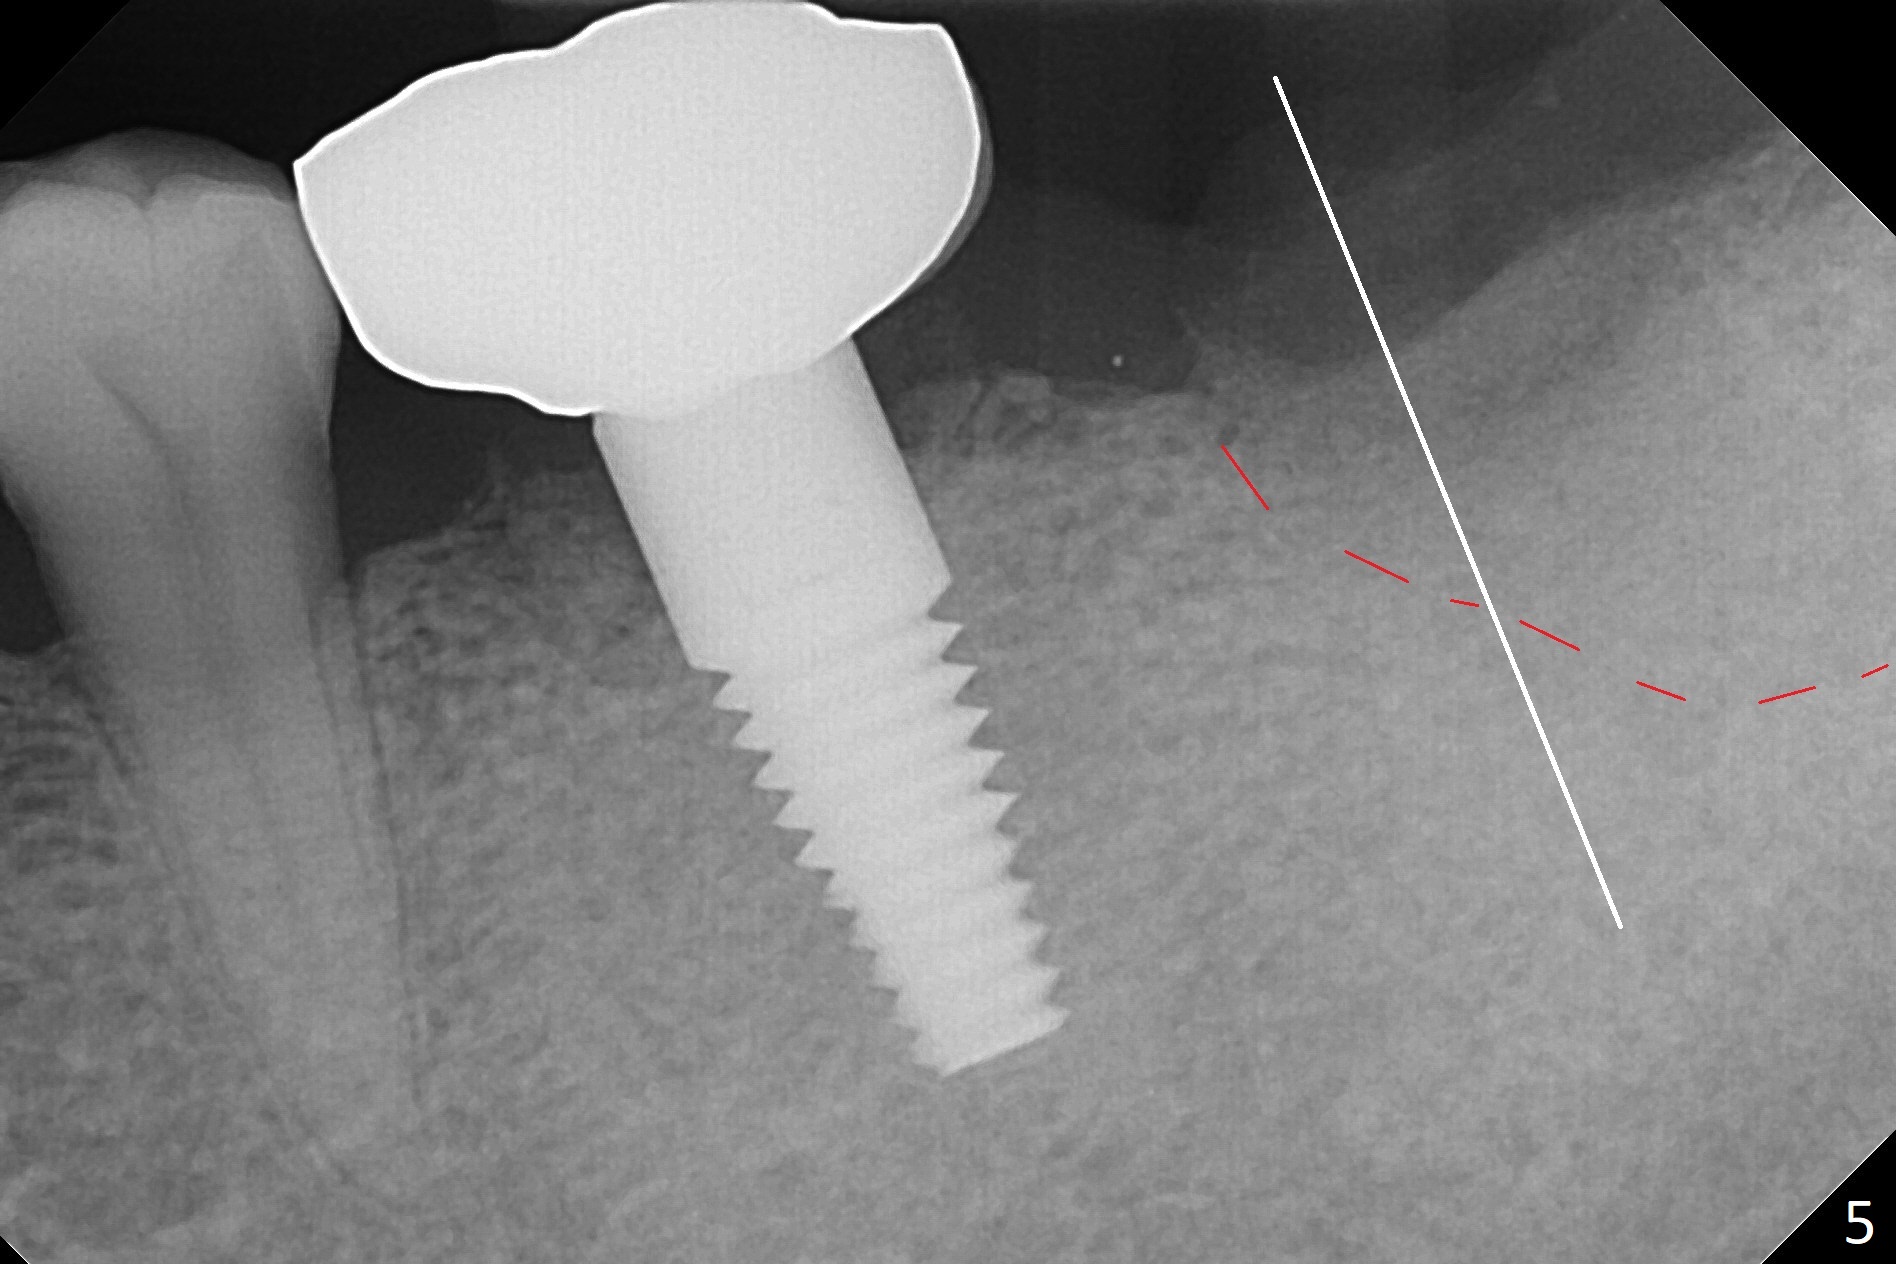

Due to severe furca (Fig.1 *) and distal root (Fig.2 D) infection at #31, there is pain when osteotomy is initiated in the apical native bone for 2 mm after extraction (Fig.3). The distal root is found to have vertical fracture. Socket preservation is performed with Vera Graft, collagen plug and 6-month membrane (Fig.4). In fact it would be possible to initiate osteotomy (Fig.5 white line) in the mesial slope (red dashed line) for implant placement (less infection (far from the lesion), less pain). There is postop pain and swelling, but the symptoms are less 7 days postop (Fig.6). The patient returns 6 months post socket preservation (Fig.7). The bone density at the healed socket is high (>1000 units); a 5x10 mm implant will be placed with guide (Fig.8). After implant placement at #18, make a buccal incision to explore the buccal gingival defect at #19 (Fig.9, 1), most likely due to extra bone graft.